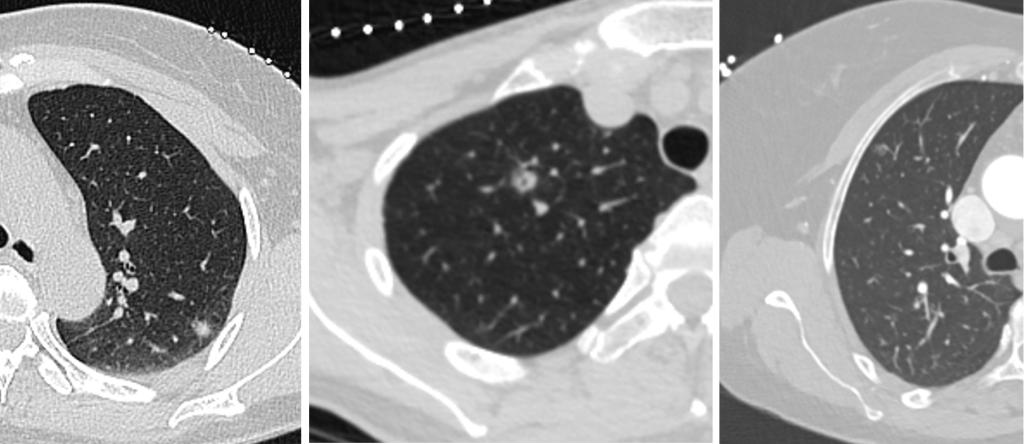

行CT引导下肺结节术前定位的几例患者均为肺内磨玻璃密度结节,且均较小,CT介入团队通过CT扫描的精准测量和定位,成功完成了手术。CT引导下肺结节术前定位技术是指在外科手术前,通过CT引导,在靶结节周围置入定位针,为手术医生在术中寻找并切除靶结节提供了精准指引。这一技术的应用,不仅提高了手术的成功率,还最大限度地减少了对周围组织的损伤。通过术前精确的定位,手术医生能够更加精准地定位到病变位置,确保手术操作的准确性和安全性,为患者带来了更小的手术风险和更短的恢复期,此外,这一技术还可以让病理科医生更准确地对标本组织进行切片,进而定性诊断。